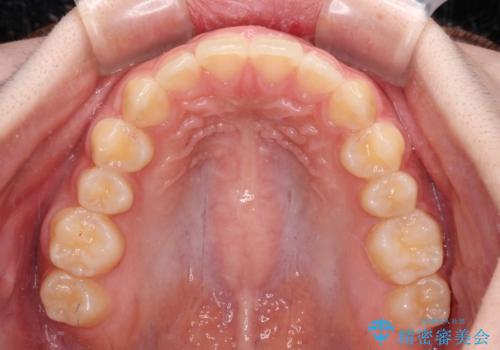

前歯のすきっ歯を治したい インビザラインによる矯正治療

- 上顎前歯の隙間を気にして来院された患者様です。

目立たない装置を希望とのことで、インビザラインを用いて矯正治療を行うこととしました。

一度インビザラインのマウスピースセットをお渡しすると1年以上来院されず、マウスピースを破損したり紛失したりすると来院されるというのんびりとしたペースで治療を行ったため、4年間という長期にわたる治療となりました。

最終的には隙間は全て閉じ、綺麗な仕上がりとなりました。